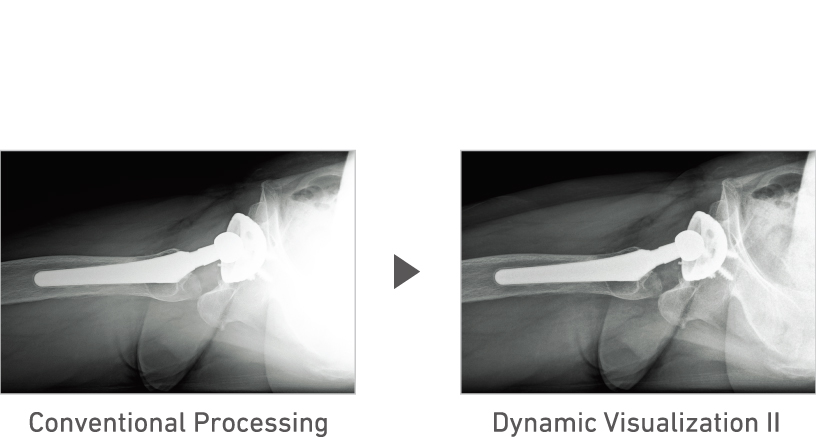

3D structure analysis technology to support mobile exam

Advanced recognition algorithms automatically adjust contrast and density for individual body parts based on calculation of estimated 3D image data.*5